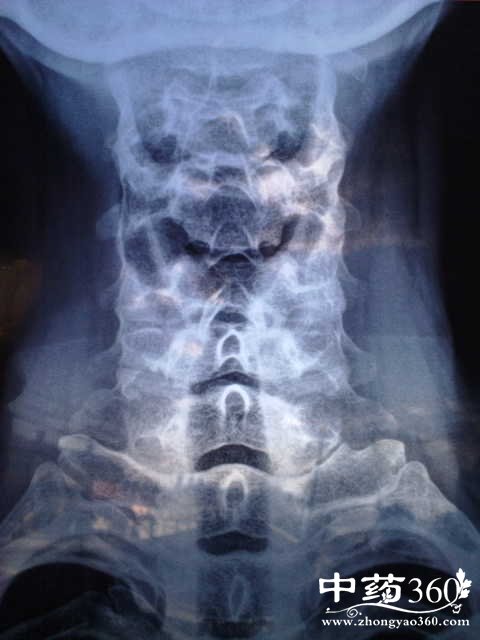

中医如何治疗颈椎病

颈椎病现在已经变成了一种通病了,以前的时候只有老年人才会颈椎不舒服,现在很多的年轻人也会患有颈椎病,是平时工作的时候没有时间活动导致的,导致颈椎病年轻化,中医是如何治疗颈椎病的呢?